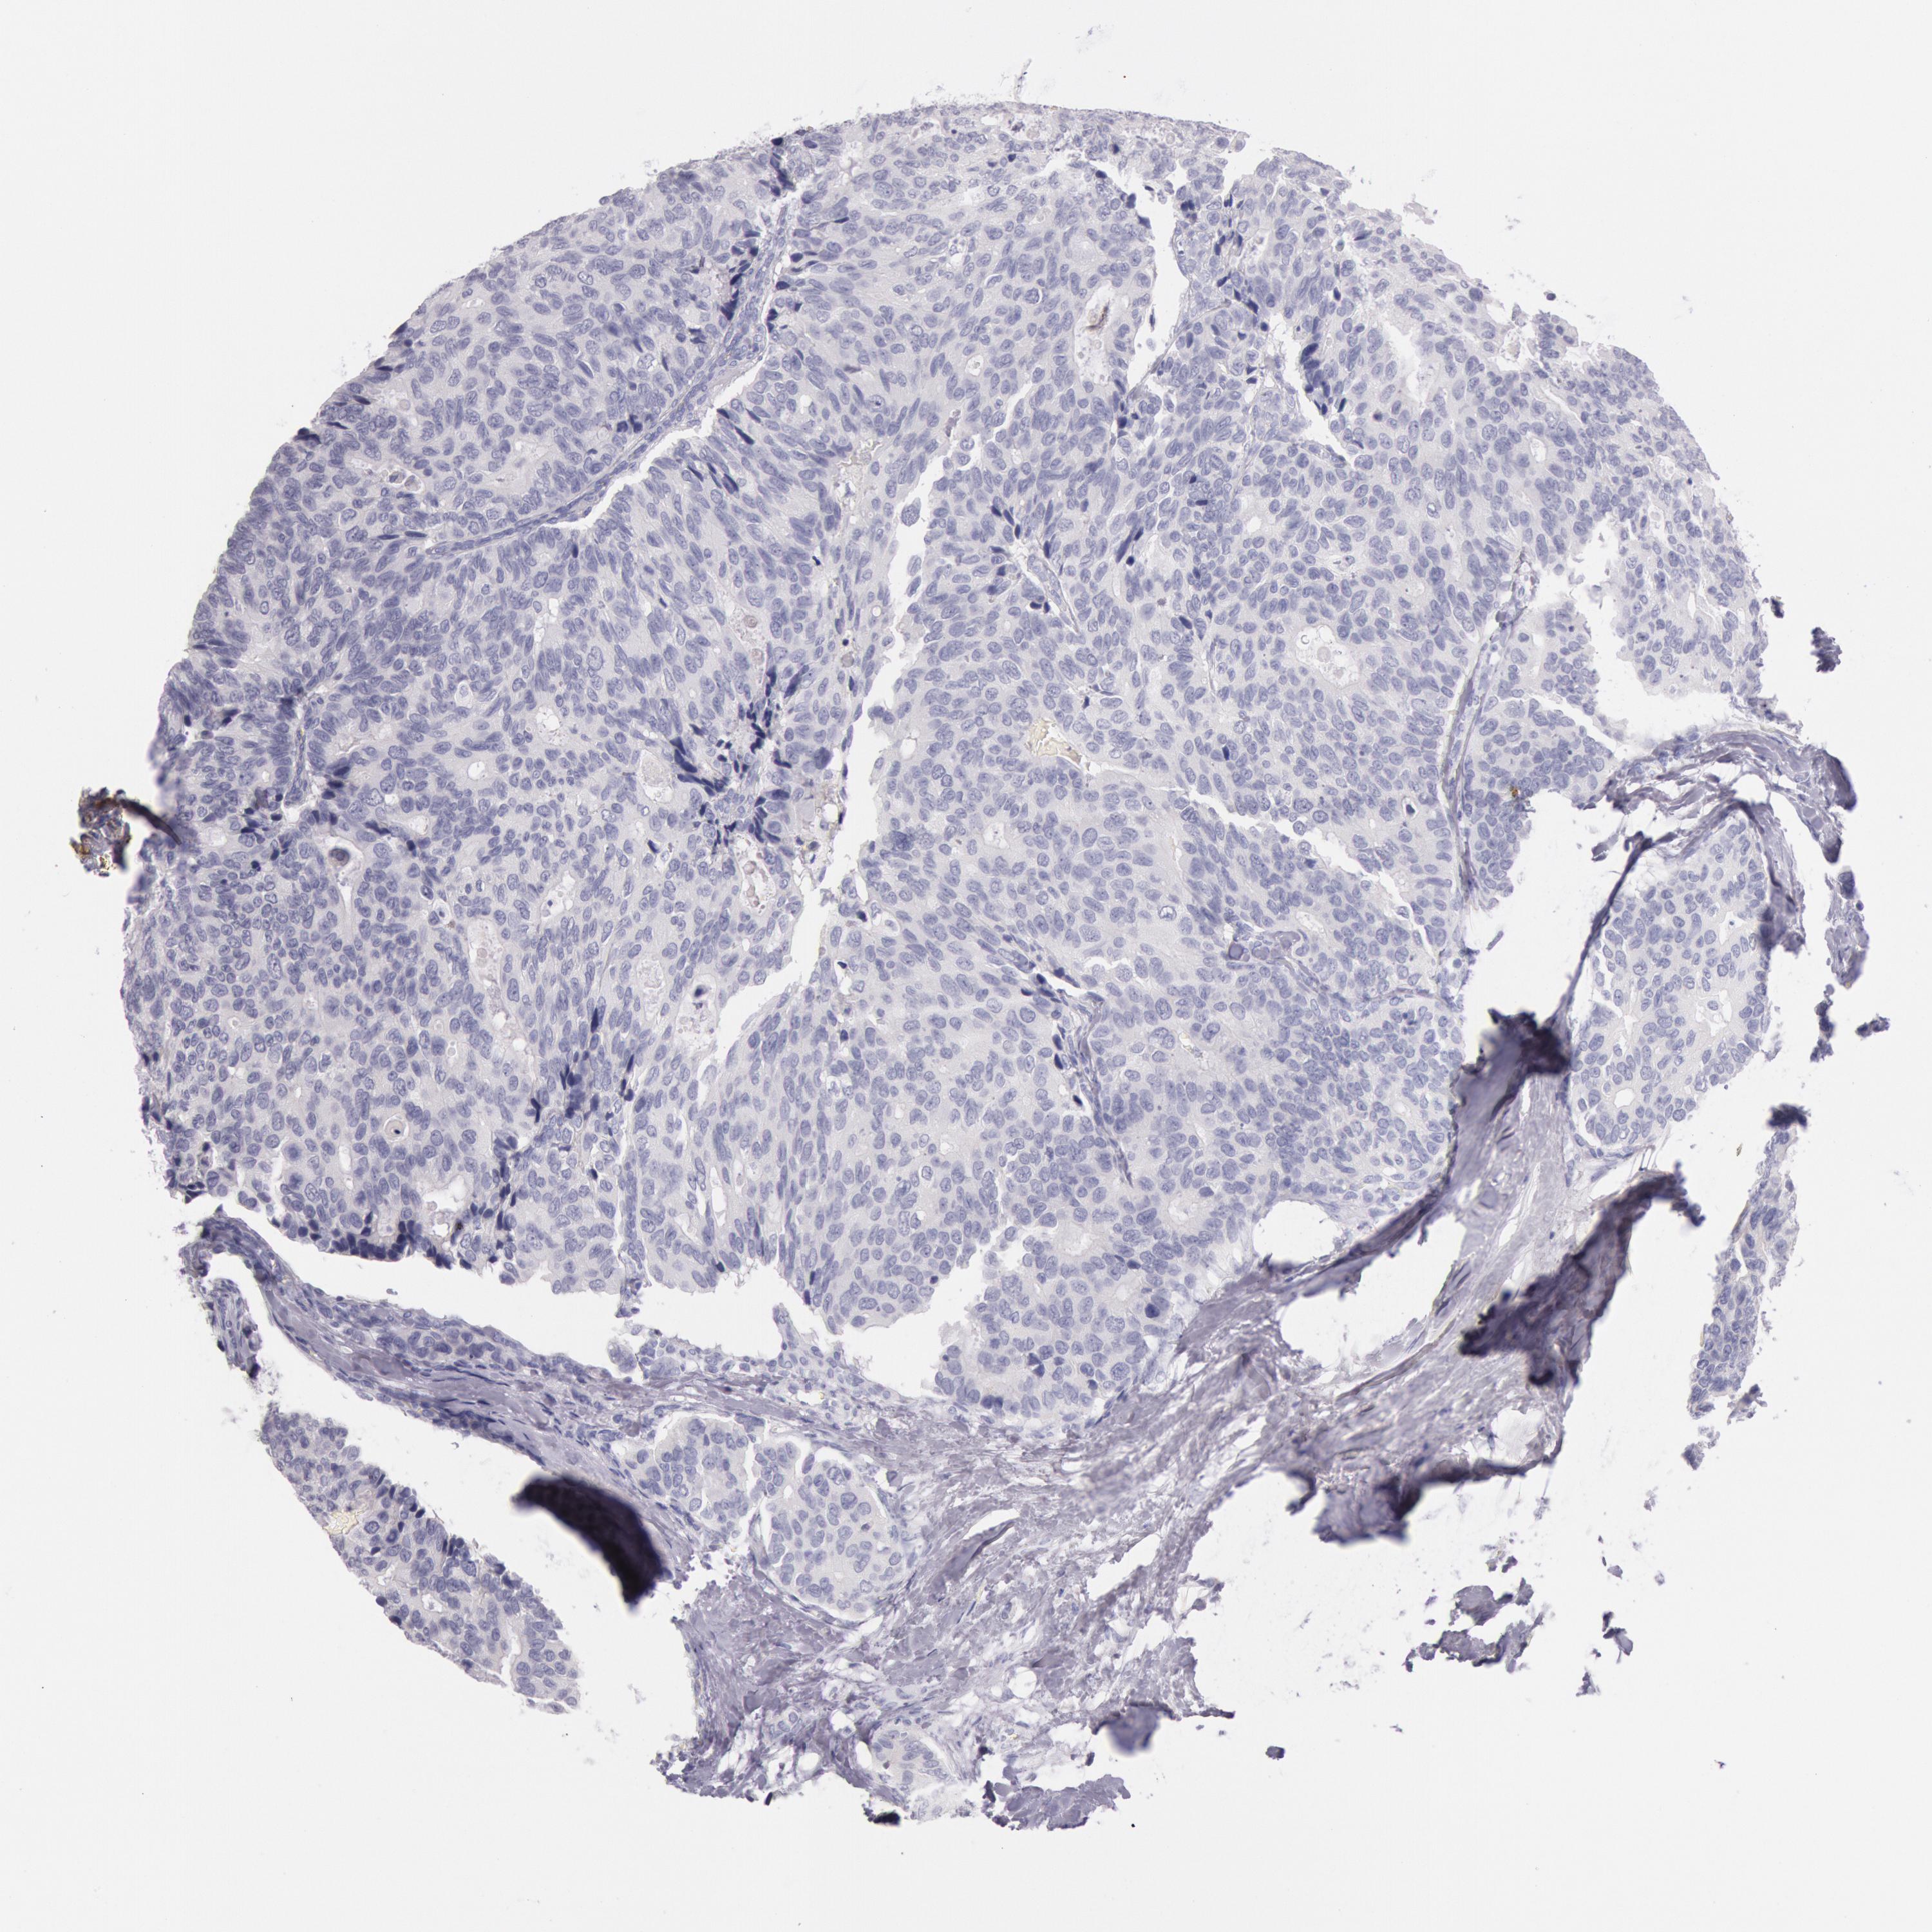

CANCER BREAST CANCER Show tissue menu

BRCA TCGA BRCA VALIDATION PROTEIN EXPRESSION

ANTIBODIES

AND

VALIDATION